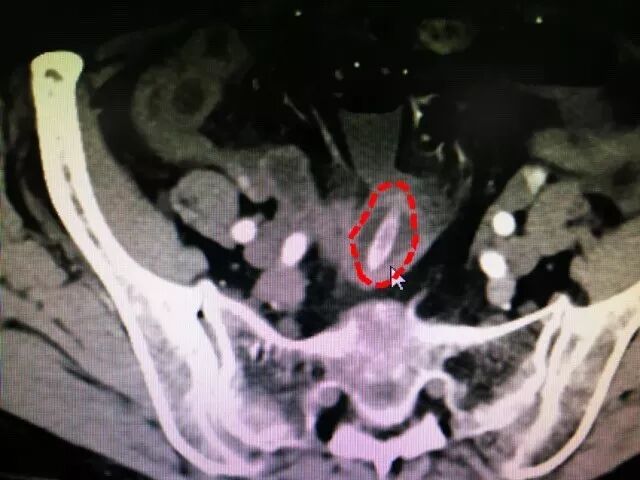

6月25日晚,老人在家属的陪同下来到医院急诊,然后CT检查也没有发现明显异常,“一直到昨天下午,她突然感到疼痛加剧,医生为她做了增强CT,发现小肠内有个异物,看起来像枣核,这时才意识到可能是红枣汤坏事了!”

(增强CT扫描后发现在小肠内的枣核 院方供图)